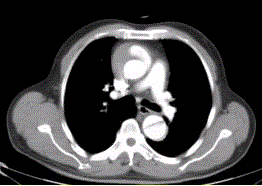

问题 患者男,67岁,高血压病史多年,自服降压药,突发胸骨后剧烈疼痛2h,服用硝酸甘油不缓解。胸透示主动脉增宽。CT影像如下图。 区分真腔和假腔最关键的征象是

选项 A.真腔通常较小 B.真腔通常位于前方 C.真腔通常血流速度慢 D.真腔的对比剂浓度通常高于假腔 E.真腔内常伴有血栓形成 F.真腔内有血管分支

答案 D